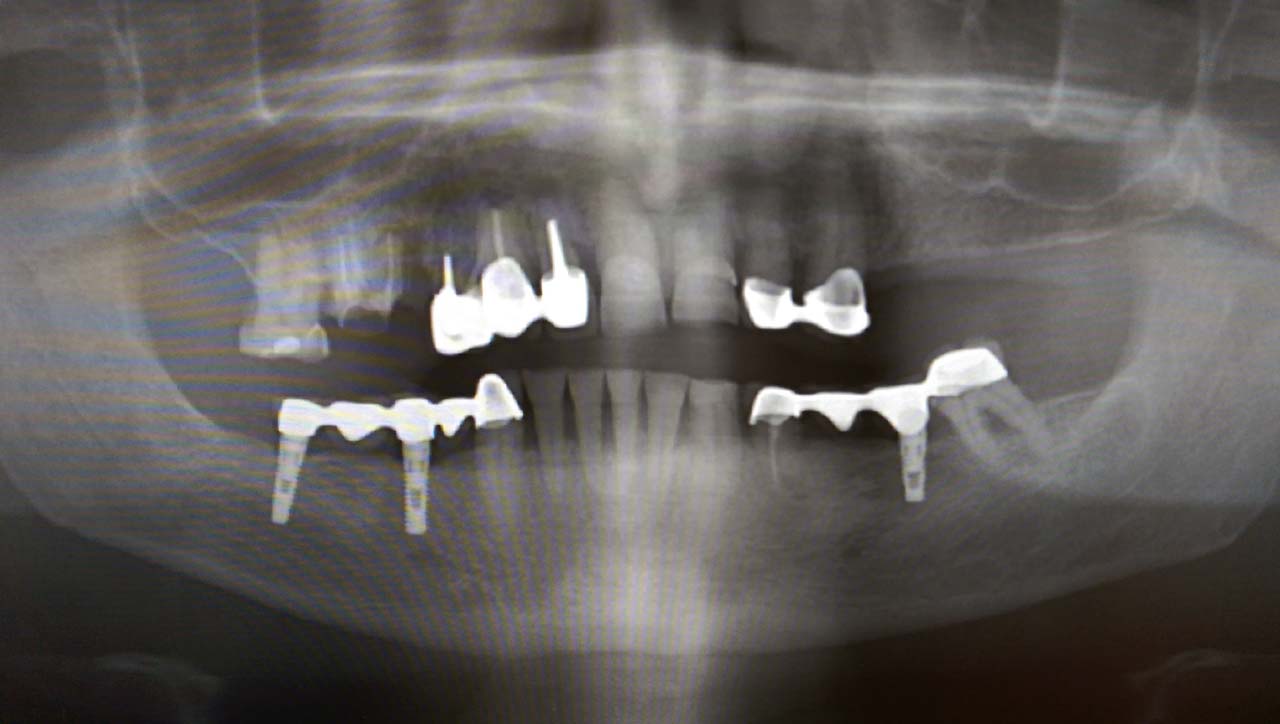

Alsó állcsont teljes rehabilitációja 72 óra alatt

Alsó állcsont teljes rehabilitációja 72 óra alatt, azonnal terhelhető implantátumokkal súlyos paradontitisben szenvedő dohányzó páciens esetében. Az alsó állcsont fogai mind mozogtak az előrehaladott fogágypusztulás miatt.

A fogakat eltávolítottuk, a gyulladt, fertőzött csontot kitakarítottuk, kifertőtlenítettük, majd azonnal implantáltunk.

Svájci, IHDE márkájú, azonnal terhelhető implantátumokat helyzetünk be, és ezekre harmadnapra rögzített, hosszútávú, fémvázas, esztétikus műanyaggal leplezett hidat ragasztottunk be.

Ezt az ideiglenes hidat a sebek gyógyulása miatt használjuk, de tartóssága miatt véglegesként is használható. A legtöbb esetben, ahogy itt is, 6 hónap múlva porcelán hídra cseréljük, a teljes gyógyulás után.